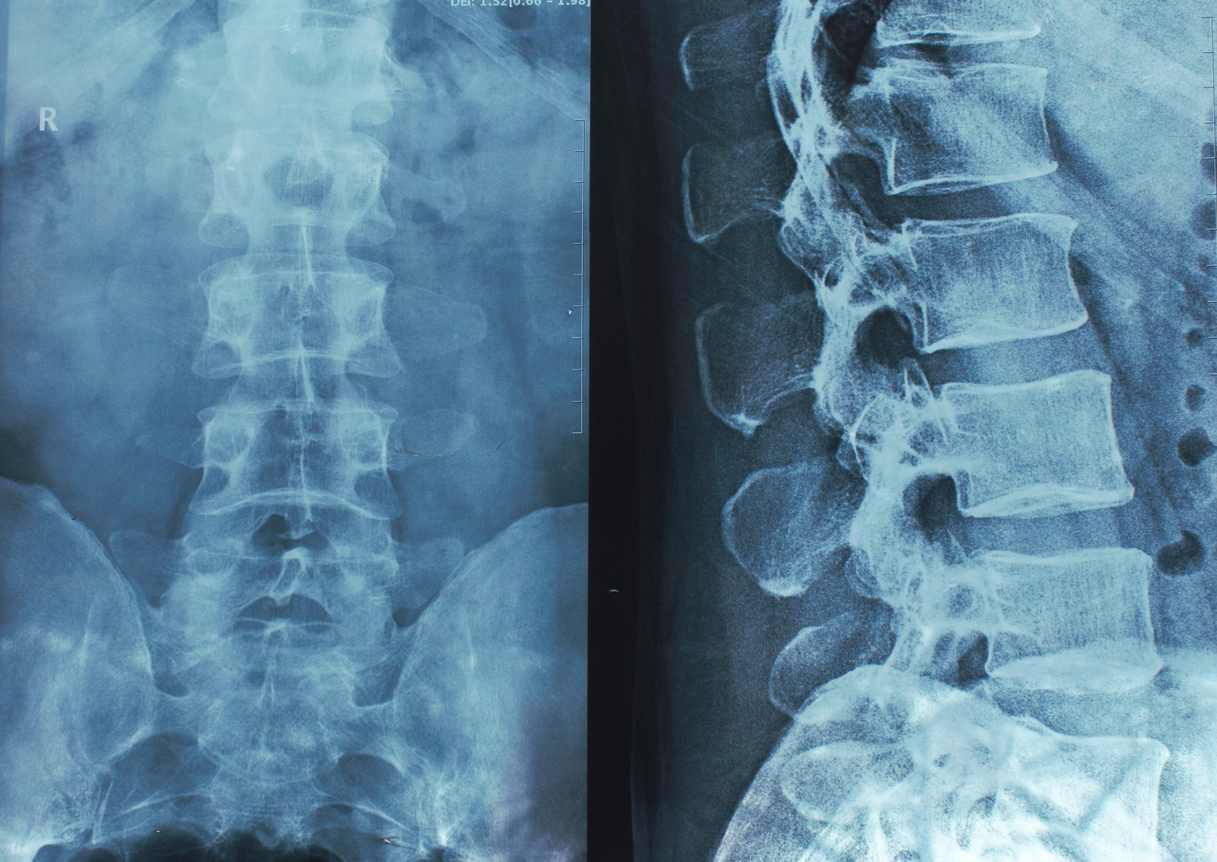

Рентген поясницы: анатомические особенности и медицинские исследования